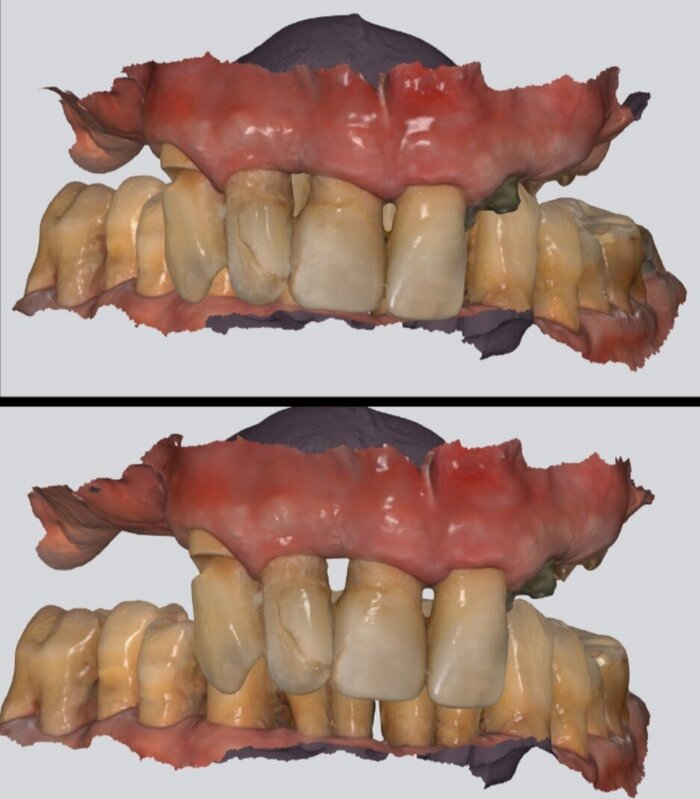

Розовый пластик - он не только спереди, он ещё и за зубами.

Временный протез "всё на 4-х", постановка на воске

На фото выше - воск. Протез временный будет поизящнее. Постоянный, когда до него дойдёт, ещё более гладкий и аккуратный получится.

Помещаем протез в полость рта, "прикручиваем" к имплантатам. Очень хорошо попали с первого же раза в комфортное положение.

Фотографируем пациента.

Протез снимается и отправляется обратно в лабораторию - техник учтёт малейшие замечания и в субботу получим протез временный в окончательном варианте.

"всё на 4-х", верхняя челюсть, временный протез адаптационный

Операция в понедельник - зубы в субботу, удобные, комфортные, в правильном прикусе. И цвет натуральный.